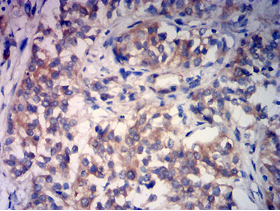

RABEP2 Mouse Monoclonal antibody[2B1B6]

This gene encodes a Rabaptin, RAB GTPase Binding Effector Protein 2. The encoded protein Plays a role in membrane trafficking and in homotypic early endosome fusion. Participates in arteriogenesis by regulating vascular endothelial growth factor receptor 2/VEGFR2 cell surface expression and endosomal trafficking . By interacting with SDCCAG8, localizes to centrosomes and plays a critical role in ciliogenesis

IHC    1/200 - 1/1000